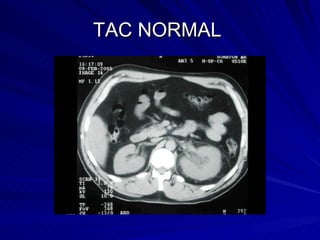

TAC NORMAL